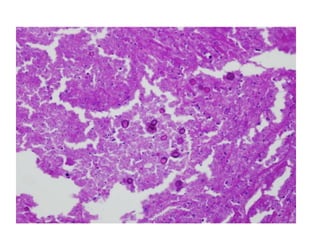

• #4 H and E stain, on the other hand, is very useful to visualize the host’s response but is not a special fungal stain. It does not stain most of the fungi, except the Aspergillus spp. and the Zygomycetes. Thus, a combination of GMS and H and E is usually employed to visualize both the tissue reaction and the infecting fungus [Figures 3 and 4]. GMS is more advantageous because it stains old and non-viable fungal elements

• #41 40 x of pnemocystis h e the organisms spread to the interstitium of the lung, widen alveolar walls, and invade blood vessel walls (arrow). Some authors believe that alveolar walls then undergo lysis to form cavities [3]. Other authors have attributed the lysis to ischemic necrosis caused by a necrotizing angiitis [4]. Note that there is little inflammatory reaction.

• #42 An adjacent section was stained with the GMS stain to show the presence of spore cases both in the alveolar space (A) and alveolar wall (W).

• #43 The foamy pink exudate stains with the PAS stain after diastase digestion. It is composed of trophic forms, surfactant phospholipids, cell debris, and host-derived proteins [2]. The faint dots in the exudate correspond to nuclei of the trophic forms.